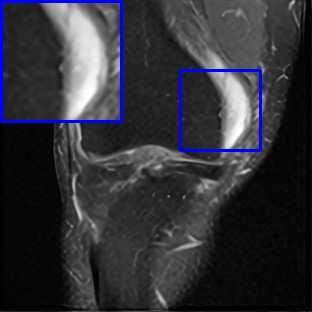

Limited by imaging systems, the reconstruction of Magnetic Resonance Imaging (MRI) images from partial measurement is essential to medical imaging research. Benefiting from the diverse and complementary information of multi-contrast MR images in different imaging modalities, multi-contrast Super-Resolution (SR) reconstruction is promising to yield SR images with higher quality. In the medical scenario, to fully visualize the lesion, radiologists are accustomed to zooming the MR images at arbitrary scales rather than using a fixed scale, as used by most MRI SR methods. In addition, existing multi-contrast MRI SR methods often require a fixed resolution for the reference image, which makes acquiring reference images difficult and imposes limitations on arbitrary scale SR tasks. To address these issues, we proposed an implicit neural representations based dual-arbitrary multi-contrast MRI super-resolution method, called Dual-ArbNet. First, we decouple the resolution of the target and reference images by a feature encoder, enabling the network to input target and reference images at arbitrary scales. Then, an implicit fusion decoder fuses the multi-contrast features and uses an Implicit Decoding Function~(IDF) to obtain the final MRI SR results. Furthermore, we introduce a curriculum learning strategy to train our network, which improves the generalization and performance of our Dual-ArbNet. Extensive experiments in two public MRI datasets demonstrate that our method outperforms state-of-the-art approaches under different scale factors and has great potential in clinical practice.